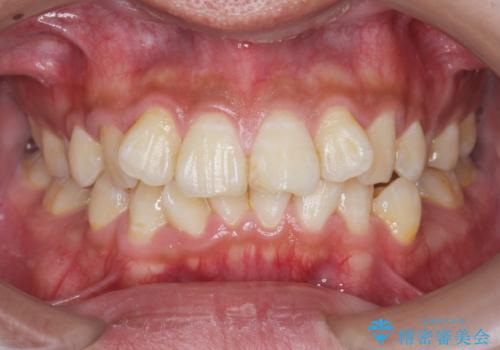

【モニター】処置歯の多い歯列 インビザラインでデコボコを整える